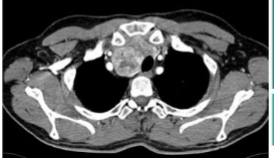

what is this and what kind of scan

tracheal displacement, CT